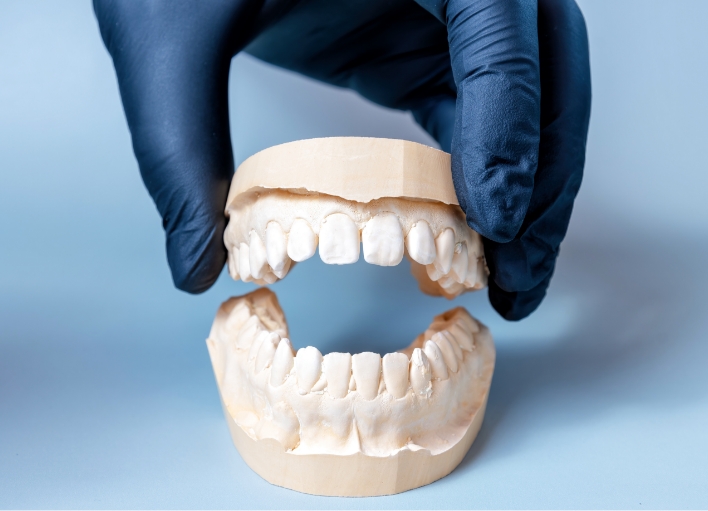

人工歯の作製・装着

歯の役割を果たす人工歯(上部構造)を作製するための型取りを行います。

1~2週間後にできあがり、作製した人工歯をかぶせ、噛み合わせなどのチェックを行います。